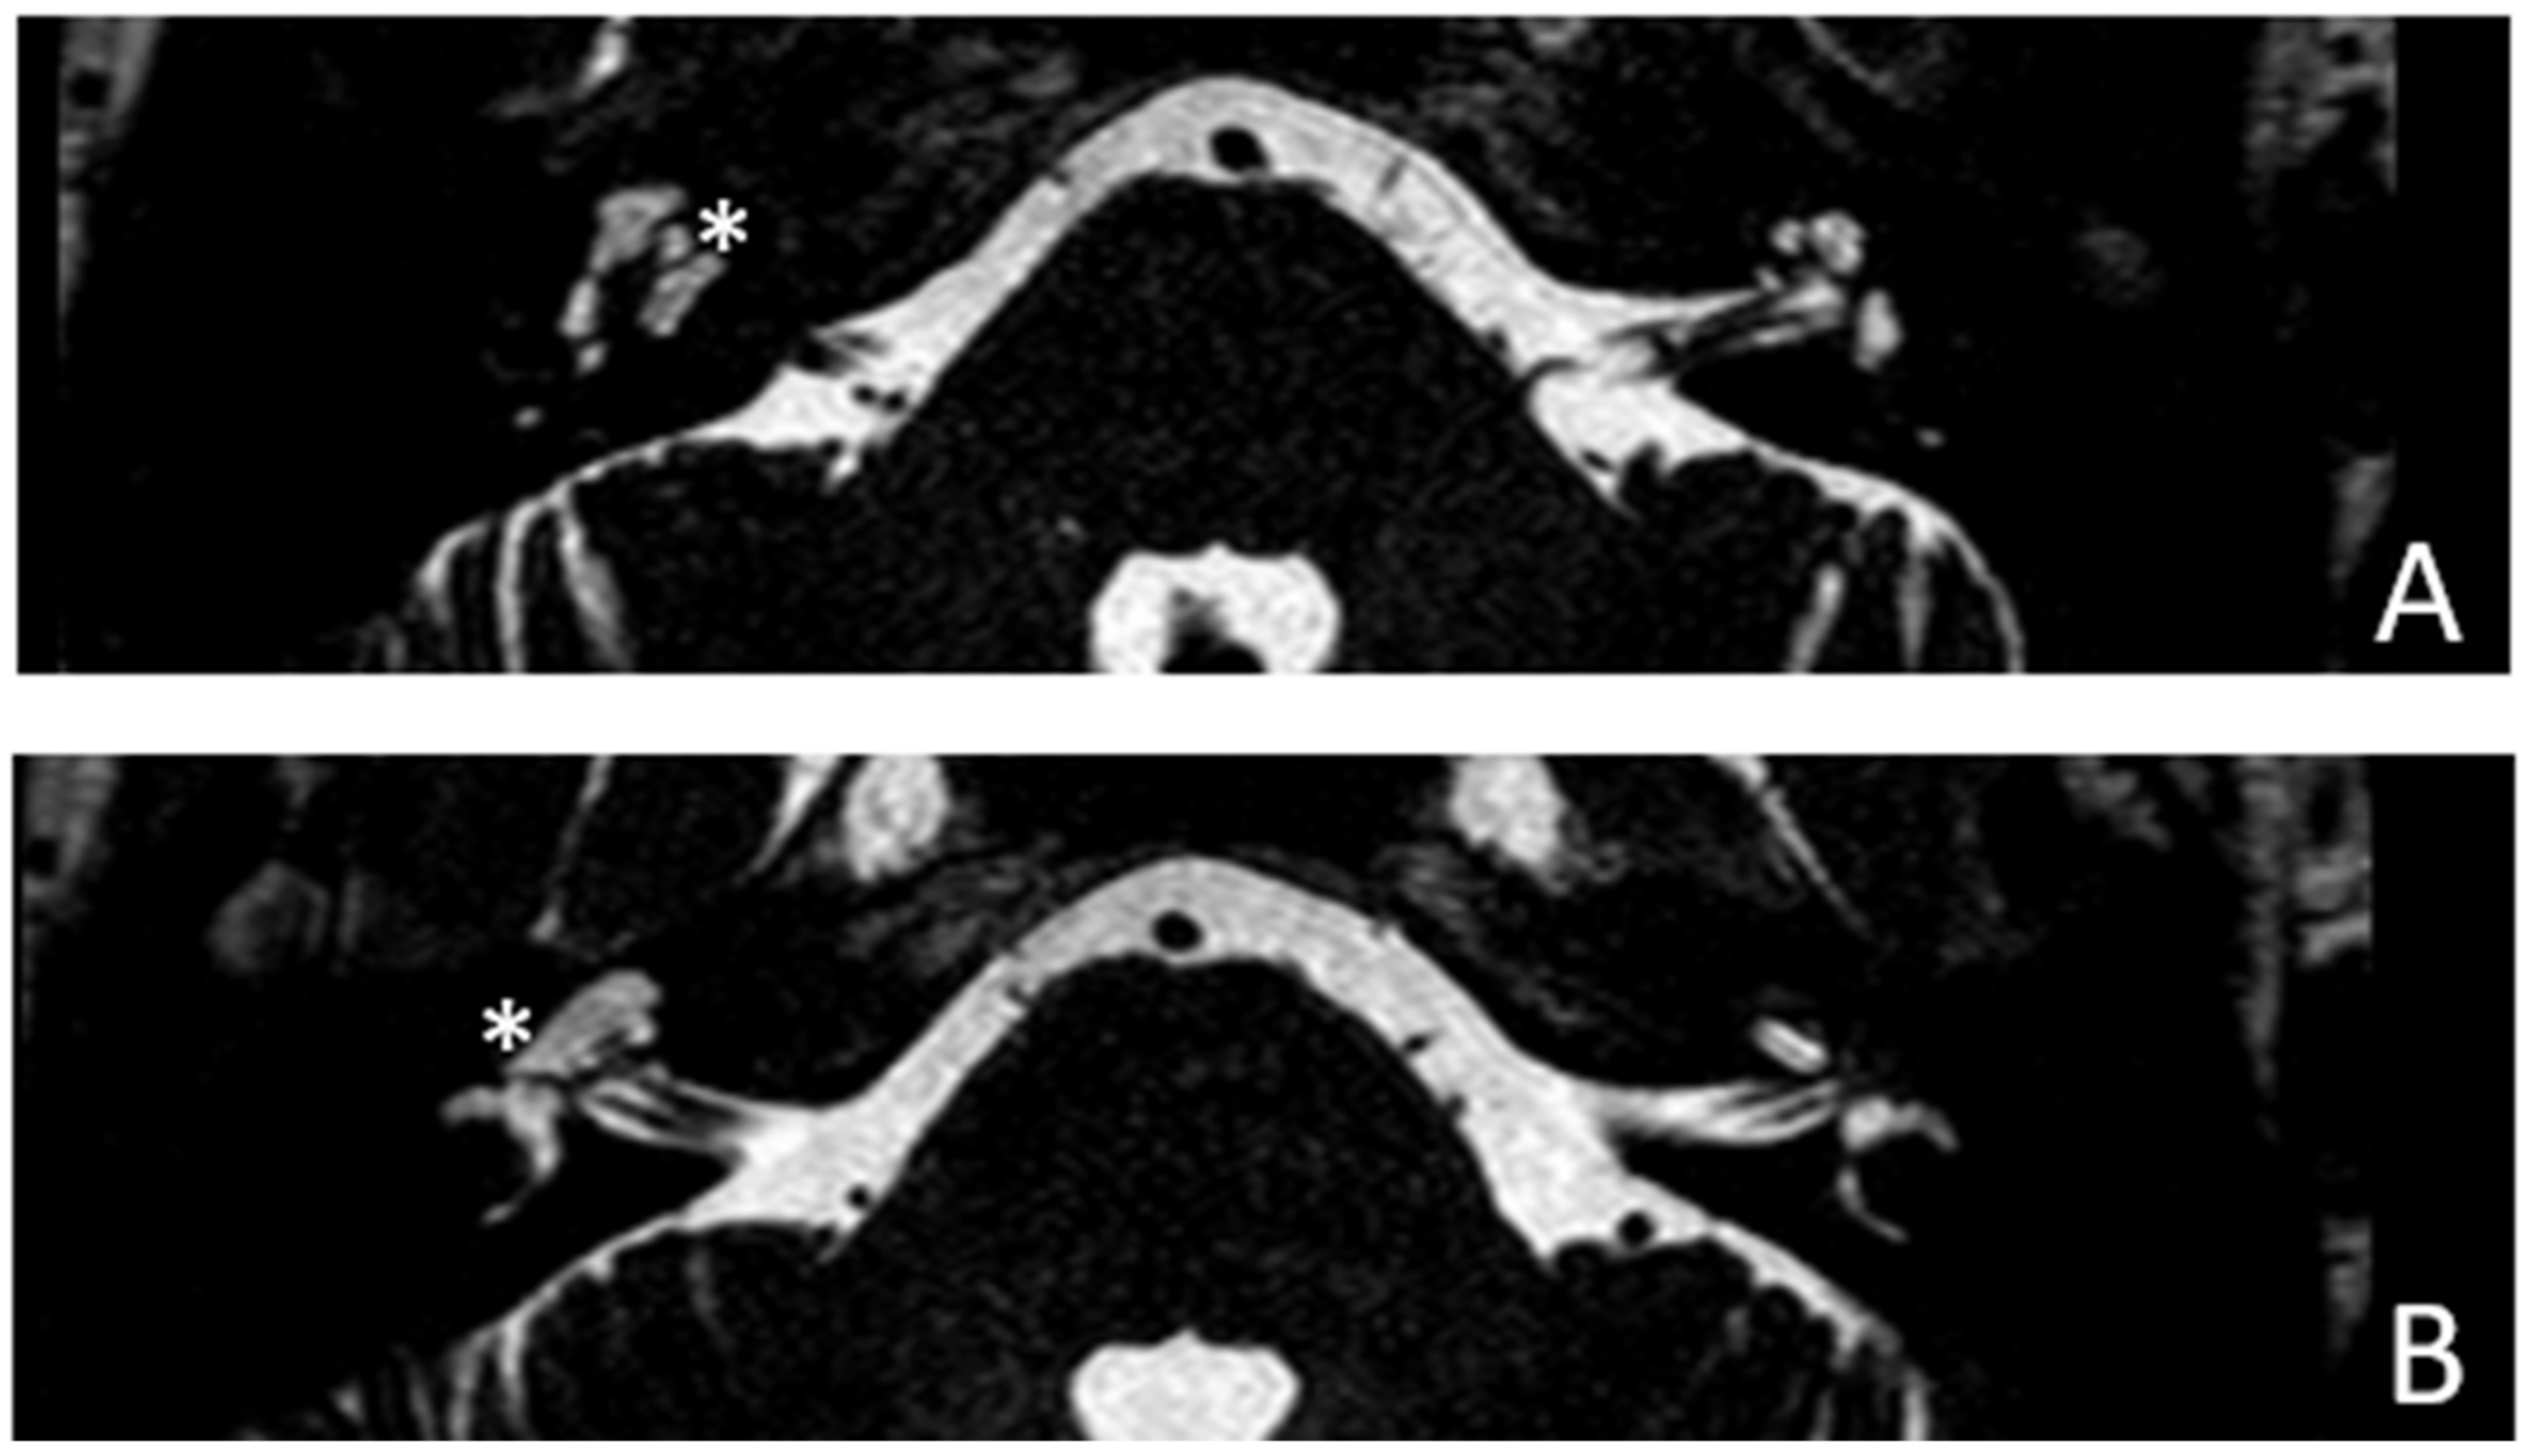

Patient #2, affected by OI-type I (COL1A1 mutation). MHL since diagnosis. Bone threshold was similar in both ears, but PTA was worse in the right ear with a larger ABG. HL progressed, but the difference between the two sides was maintained. The patient was fitted with conventional hearing aids bilaterally. Stapes surgery was not performed because of the radiological aspect (Figure 3 and Figure 4): a large cavity is present bilaterally and diffused communication between the cavity and the cochlea is evident.

Figure 4. MR images of patient #2 with osteogenesis imperfecta. MR cisternography: (A), axial plane; (B), coronal plane. Note the fluid-signal in the newly formed cavities (white asterisk).